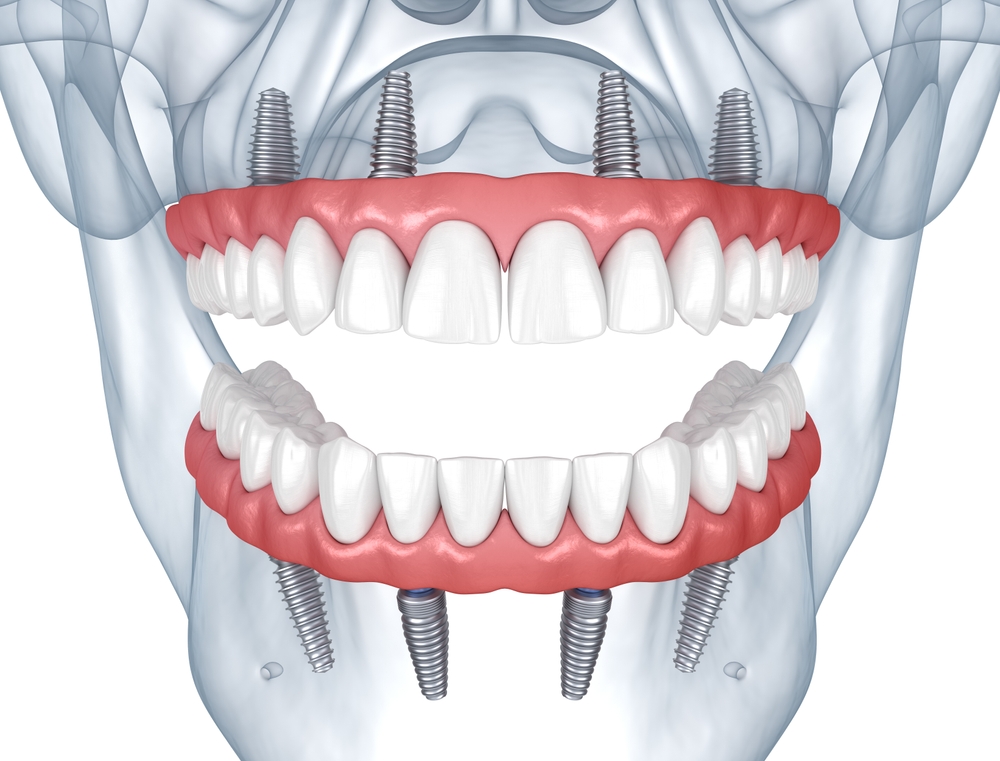

All-on-4® is an innovative dental procedure designed to provide a permanent, full-arch restoration for individuals with missing teeth. This solution combines the latest in dental technology with advanced surgical techniques to offer a comprehensive and efficient treatment option. Here's what you need to know:

All-on-4 dental implants provide a revolutionary solution for those looking to restore their smile and dental function efficiently and effectively. This procedure represents a significant advancement in dental care, offering hope and improved quality of life for many. Even if you don't need a full-arch restoration, you can benefit from our single or multi-tooth dental implants in Glendale, AZ for individual tooth replacement.

All-on-4® is a fixed full-arch bridge supported by four strategically placed implants — often with tilted posterior implants to maximize bone contact and avoid anatomical structures like sinuses.

The All-on-4® protocol uses four implants per arch. Some patients benefit from six implants (All-on-6) depending on bone density and bite forces. We determine this with CBCT imaging.